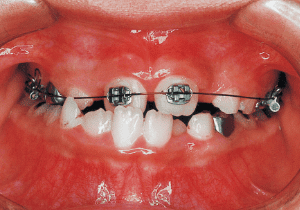

On the lateral cephalometric radiograph, the vertical height of the face appears greater than its depth. The lower facial height is also high, suggesting a shape somewhat prone to developing a protruding lower bite, though this does not raise significant concern (6). The facial photograph of front view shows slight asymmetry in the face, but it is not particularly extreme (1). The first phase of treatment corrected the anterior cross bite and deviation, but subsequent growth exacerbated the mandibular deviation, necessitating surgical treatment.

The Edgewise appliance was applied locally (8) and removed after 11 months (9). However, as the maxillary molar region gradually became crossbite, the maxillary arch was laterally expanded using a quad helix.

A case of diverted and cross bite during the deciduous dentition. Despite early treatment, the deviation progressively worsened with age, necessitating surgical treatment. At the initial visit, the patient had a deciduous dentition, and observation was planned (3). With the eruption of the permanent incisors, the mandible shifted slightly to the right, resulting in a cross bite (1) At this point, asymmetry can be confirmed in the front view. However, it is slight. The cephalometric X-ray reveals a structure with a slightly dominant mandible, but asymmetry in the mandibular ramus is not observed.